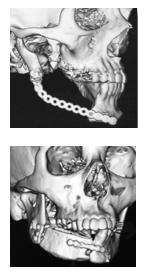

腫瘍切除後の再建外科:最近の進歩 (形成外科advanceシリ-ズ)